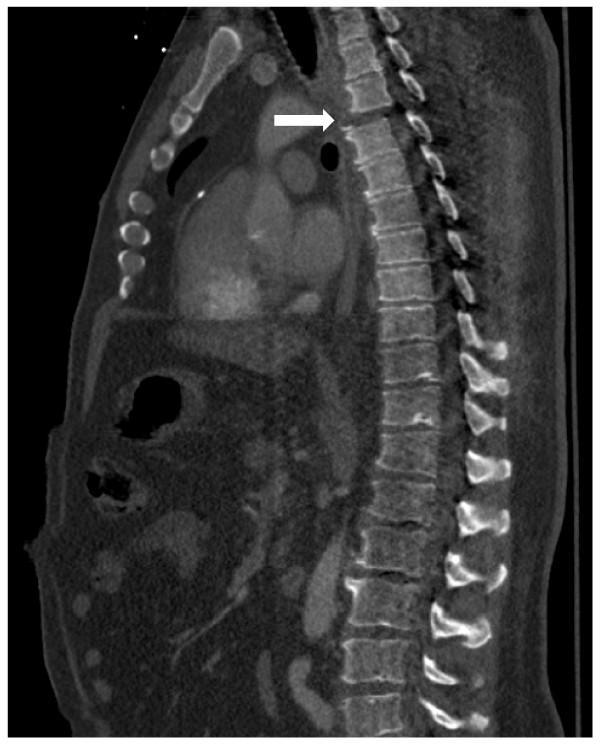

A 51 year old male presented as a tier one trauma code due to an automobile versus bicycle collision. His examination and radiographic work-up revealed fractures and a subluxation at the third and fourth thoracic spine levels resulting in paraplegia. He also sustained bilateral hemothoraces secondary to multiple rib fractures. Drainage of the left hemothorax led to the diagnosis of a traumatic chylothorax. The thoracic spine fractures were addressed with surgical stabilization and the chylothorax was successfully treated with drainage and dietary manipulation.

一名 51 岁男性因汽车与自行车碰撞而被列为一级创伤患者。他的检查和影像学检查显示第三和第四胸椎水平的骨折和半脱位导致截瘫。他还因多发性肋骨骨折而导致双侧血胸。左侧血胸引流导致外伤性乳糜胸的诊断。胸椎骨折采用手术固定,乳糜胸通过引流和饮食管理成功治疗。